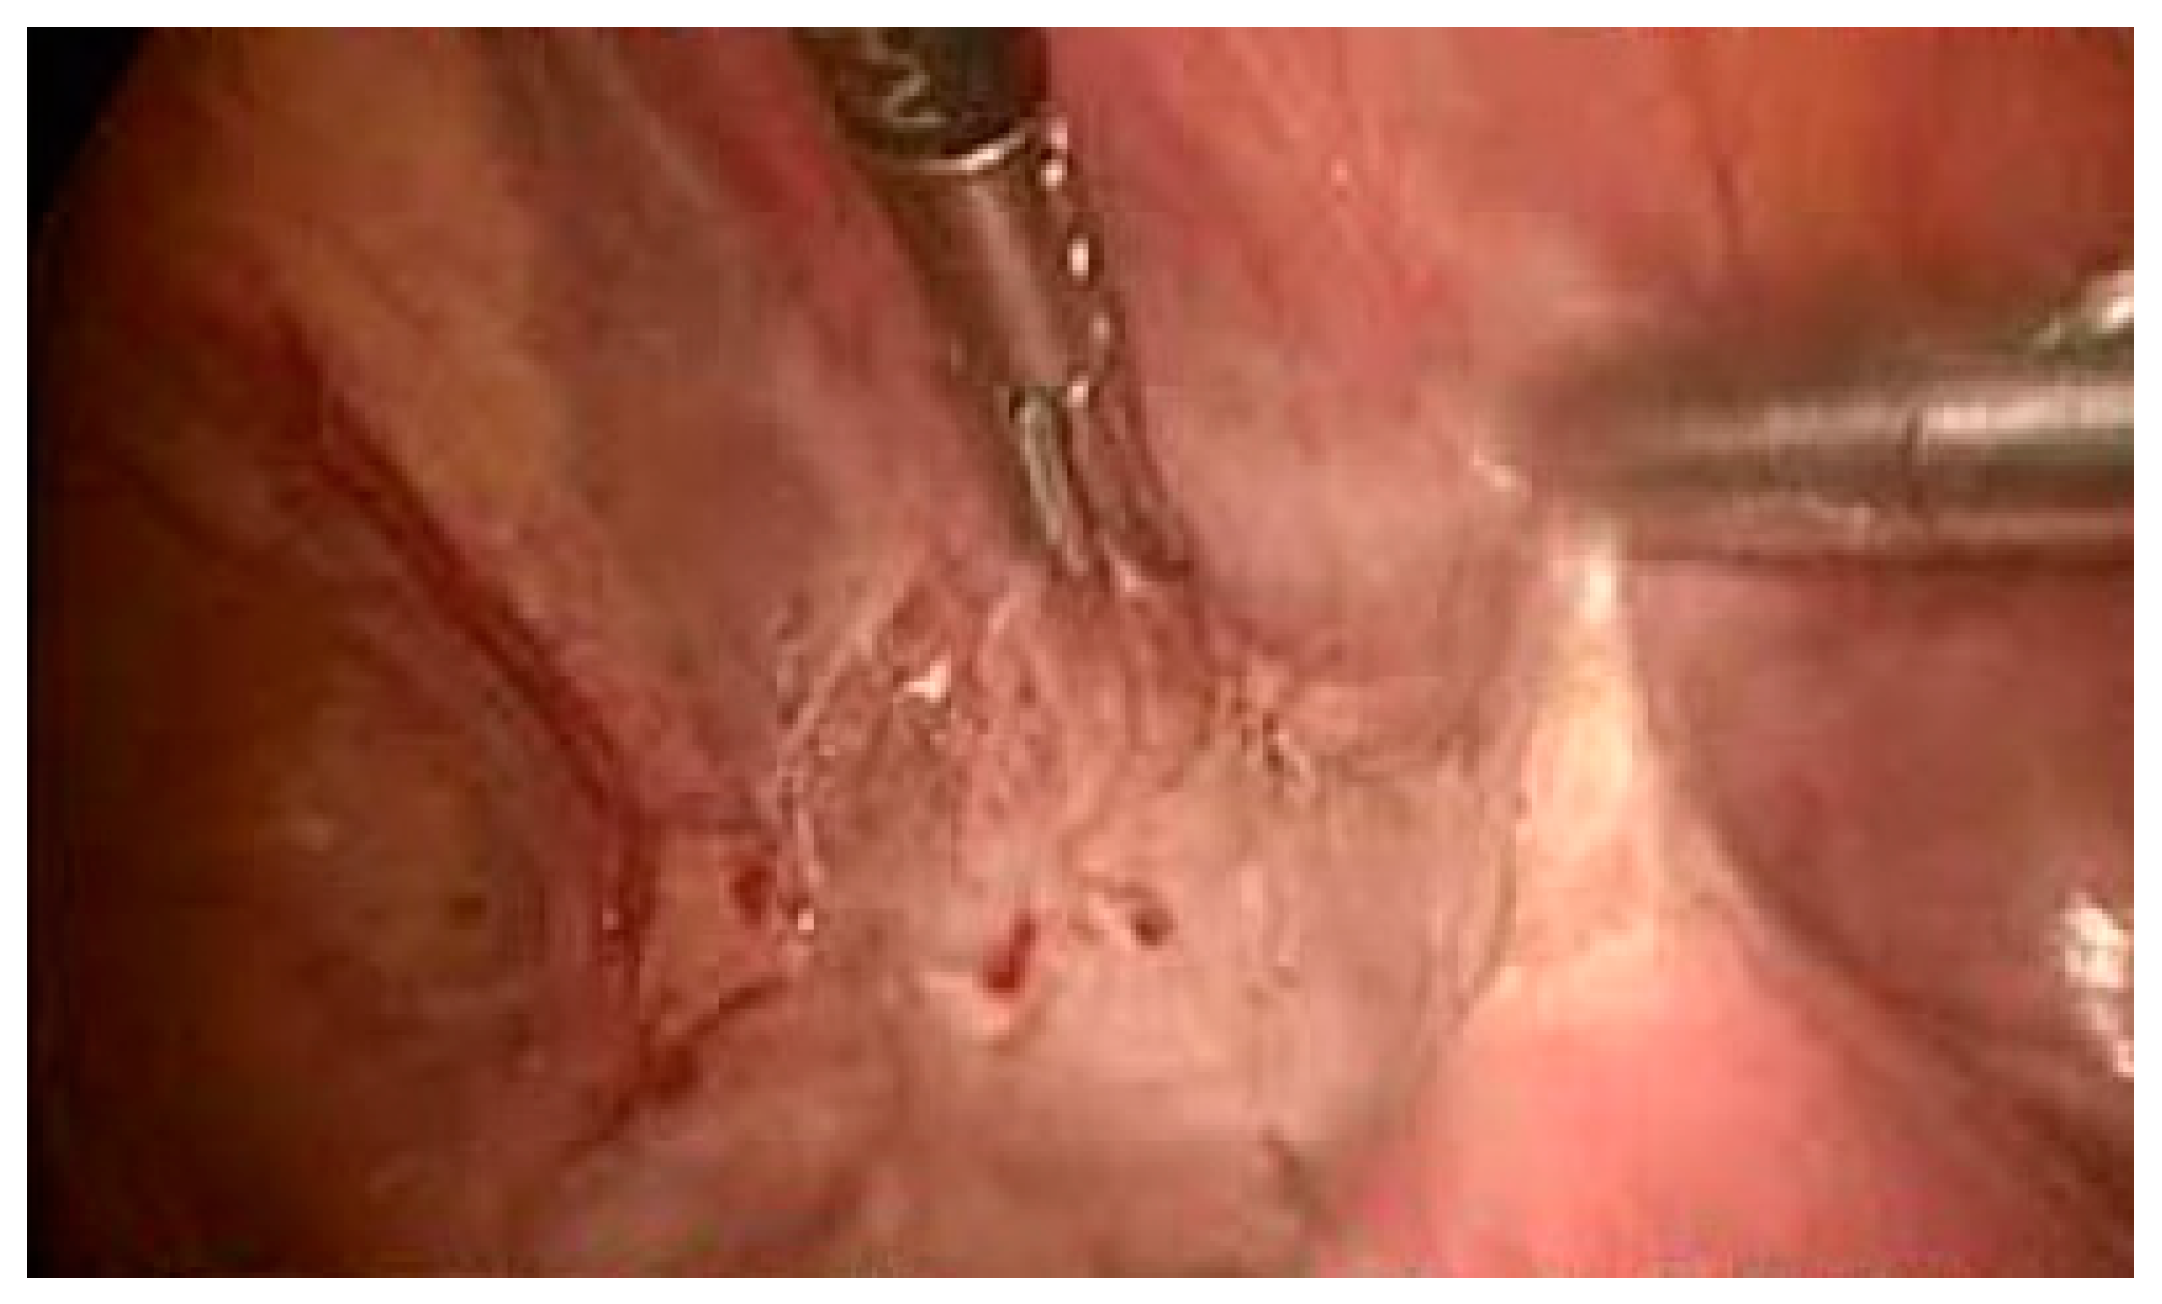

Upon arrival at our emergency department, the clinical examination showed pain when pressing at the hypogastric area as well as unclear Blumberg sign. A transvaginal ultrasound was performed, revealing abundant hemoperitoneum with an embryo of 64 mm with positive cardiac activity, 5 mm from the bladder within an invasion. Due to the threat of hemoperitoneum, transvaginal ultrasound was enough for the diagnosis of massive hemoperitoneum without requiring any additional tests and the suspicion of CSEP, and a diagnostic laparoscopy was performed and revealed massive hemoperitoneum with abundant blood clot. When a rupture on the anterior aspect of the lower uterine segment with output of decidual material was found along with significant active bleeding that was difficult to control by laparoscopy, we proceeded to open surgery. A wide uterine rupture was identified at the level of the uterine segment, through which the amniotic sac protruded and was expelled. Due to profuse bleeding after expulsion of the gestation together with the placenta and integral membranes, a subtotal hysterectomy was performed (Figure 4). The postoperative period was successful and on the fourth day, the patient was discharged. The pathologic anatomy revealed rupture on the anterior surface of the uterus measuring 2.8 × 2.5 cm. The endometrial mucosa protruded through the solution of continuity. When the uterine cavity was cut, an endometrium with a thickness of 1.1 cm was observed.

Figure 4. A 13-week visible gestational sac and prolapse after rupture of the uterine segment.